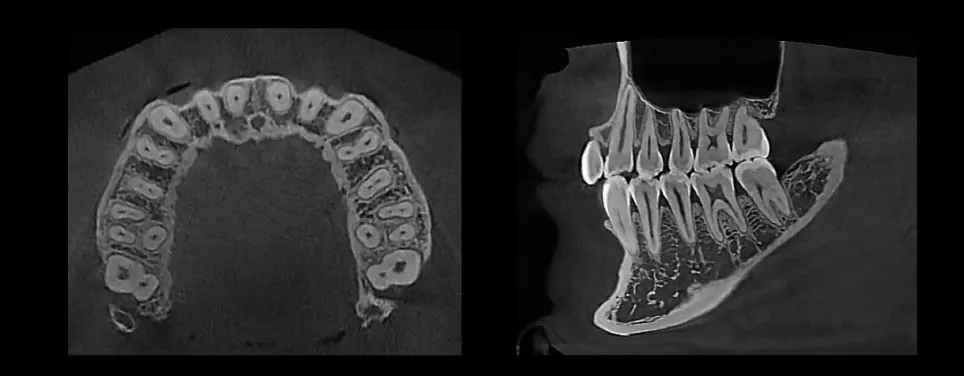

Superior Image Quality

Striking contrast and sharpness of images produced by HDX WILL’s image reconstruction technology

Wide FOV ( Max 16 x 9 cm)

Wide FOV gives the flexibility to capture the dentition, TMJ, or sinus